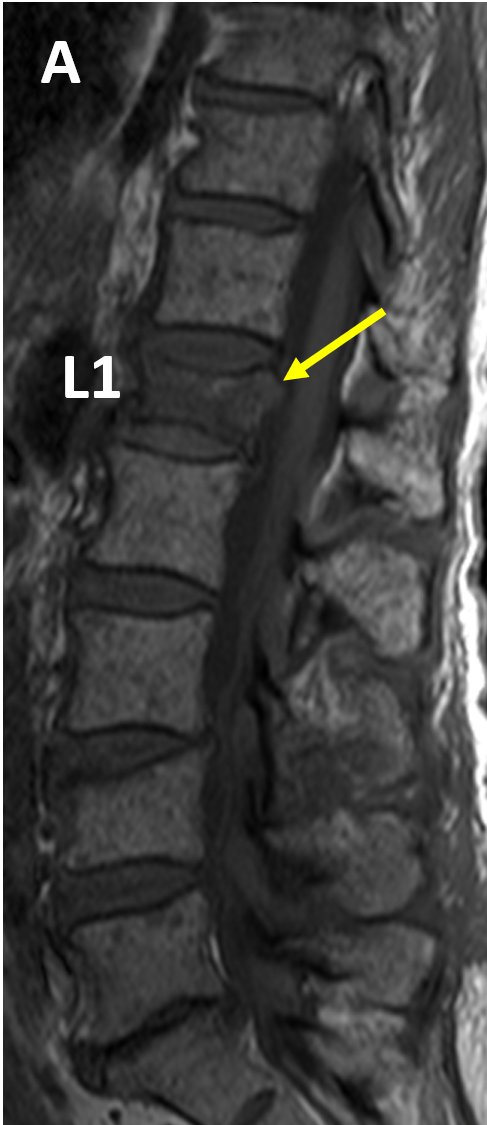

Multiple Sclerosis (MS) of the Spine - https://hubs.ly/H0mPrFV0 by

@jannimd Spinal MS is often associated with brain lesions; however, 20% of patients with spinal lesions do not have intracranial plaques#RadRes#FOAMRadpic.twitter.com/pskcyG8AzA